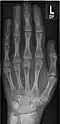

- Röntgenaufnahmen der Handknochen von Kindern unterschiedlichen Alters

Mädchen, 14 Jahre -

Junge, 14 Jahre